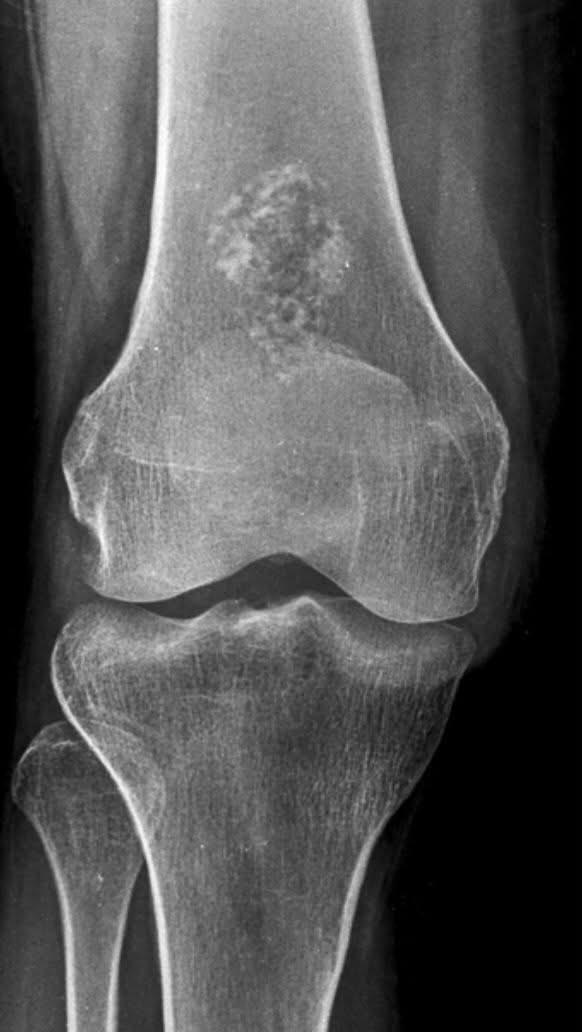

Diagnose the lesion on this X-ray ?🩻 #Orthopedics #XRay #Tumors #Health

hemo_shk's tweet image. Diagnose the lesion on this X-ray ?🩻

#Orthopedics #XRay #Tumors #Health